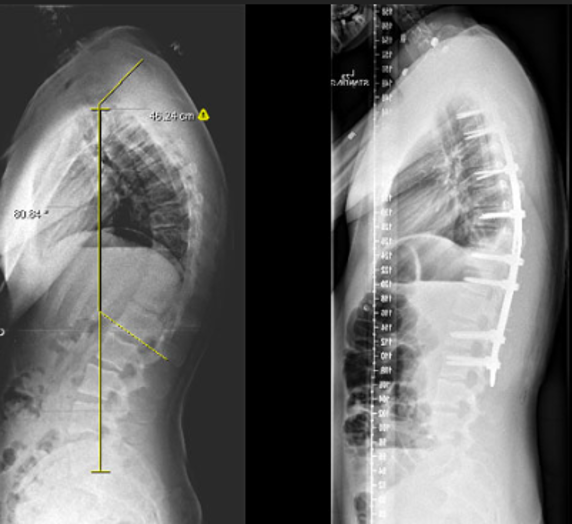

Spinal Deformity Correction (Scoliosis and Kyphosis)

Correcting abnormal spinal curvatures for better alignment and function.

Surgery to straighten and stabilize an abnormally curved spine using rods, screws, and fusion.

Curves are corrected with rods and screws. The bones are fused to maintain correction permanently.

- Straighter spine and improved appearance